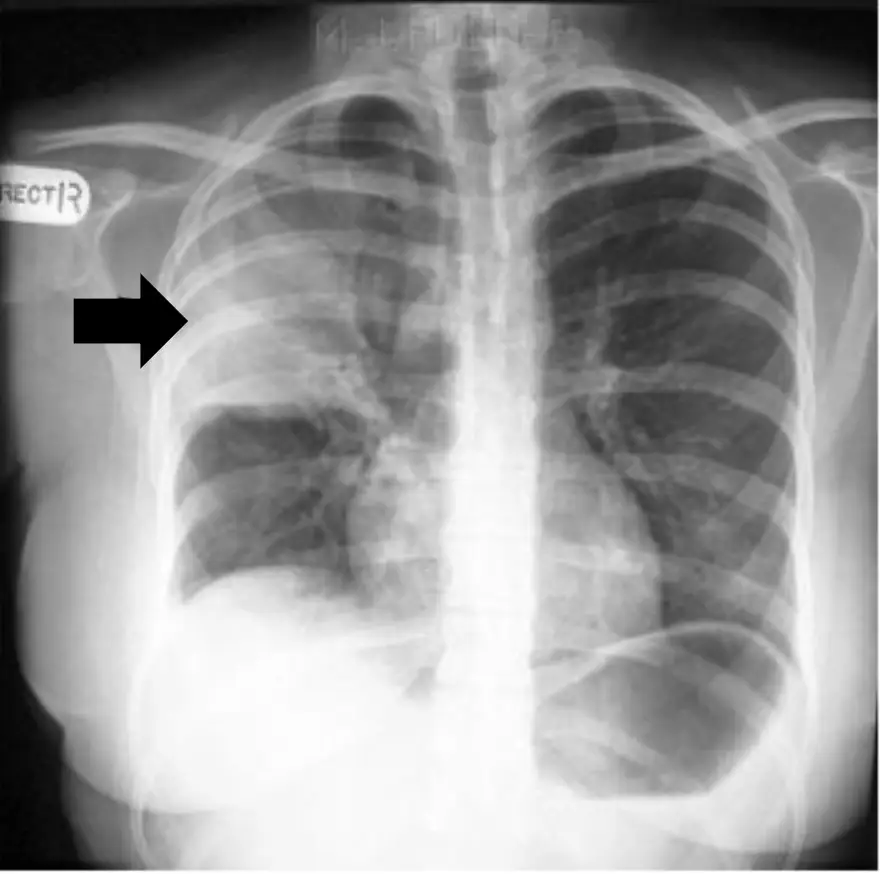

一位75歲女性糖尿病患,本次因發燒、咳黃痰住院,診斷為社區性肺炎,胸部X光片如下 圖,下列何者是箭頭所指的變化?

本題考的觀念是:胸部 X 光判讀中「社區性肺炎的典型肺部影像—肺實變 (consolidation)」之辨識與鑑別。影像上看到的實變代表肺泡被發炎滲出液取代,為診斷 CAP 的關鍵條件之一。

• 影像特徵:箭頭所指區域呈現均質、邊緣較模糊的片狀高密度陰影,且可見支氣管充氣徵 (air-bronchogram);無明顯體積減少或牽拉,符合肺實變。

• 病理意義:肺泡腔被纖維素性滲出液、發炎細胞與微生物充填,氣體被排擠而產生實質化陰影。這正是 CAP 的典型影像表現,也是診斷時「臨床症狀 + 影像浸潤」的必要條件。 -

A. 肺空洞 (cavity)- 影像通常呈圓形或橢圓形透亮區,邊緣可厚可薄,可伴空氣液體面;題目影像為實心陰影而非透亮。

C. 肺腫瘤 (mass) - 腫瘤常呈圓形或分葉狀實心結節,邊界較清晰,可伴鈣化或胸膜凹陷;本例為弥漫片狀陰影且病程急性,不符腫瘤表現。

D. 肺塌陷 (atelectasis) - 典型徵象為容積縮小、縱膈或裂縫移位,牽拉周圍組織;影像中未見明顯體積減少,也無牽拉徵象。